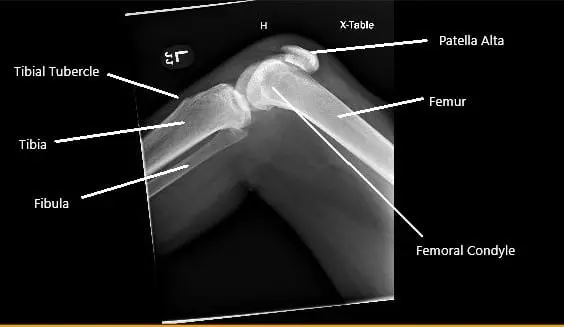

A sulcus was palpable in front of the left knee and the patient was unable to perform a straight leg raise test. The examination of the bilateral hips and spine was normal. There was ecchymosis in front of the left knee. X-ray of the left knee revealed a patella Alta and the presence of soft tissue swelling.

X-ray of the right knee showing patella Alta secondary to the rupture of the patellar tendon